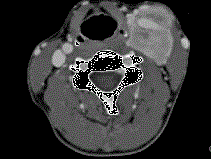

问题 女,39岁,左颈部可扪及一肿块,无发热,无疼痛,CT如图所示,最可能的诊断是 ( )

选项 A、颈部海绵状血管瘤 B、颈动脉瘤 C、颈动脉体瘤 D、颈部神经纤维瘤 E、颈部神经鞘瘤

答案 C